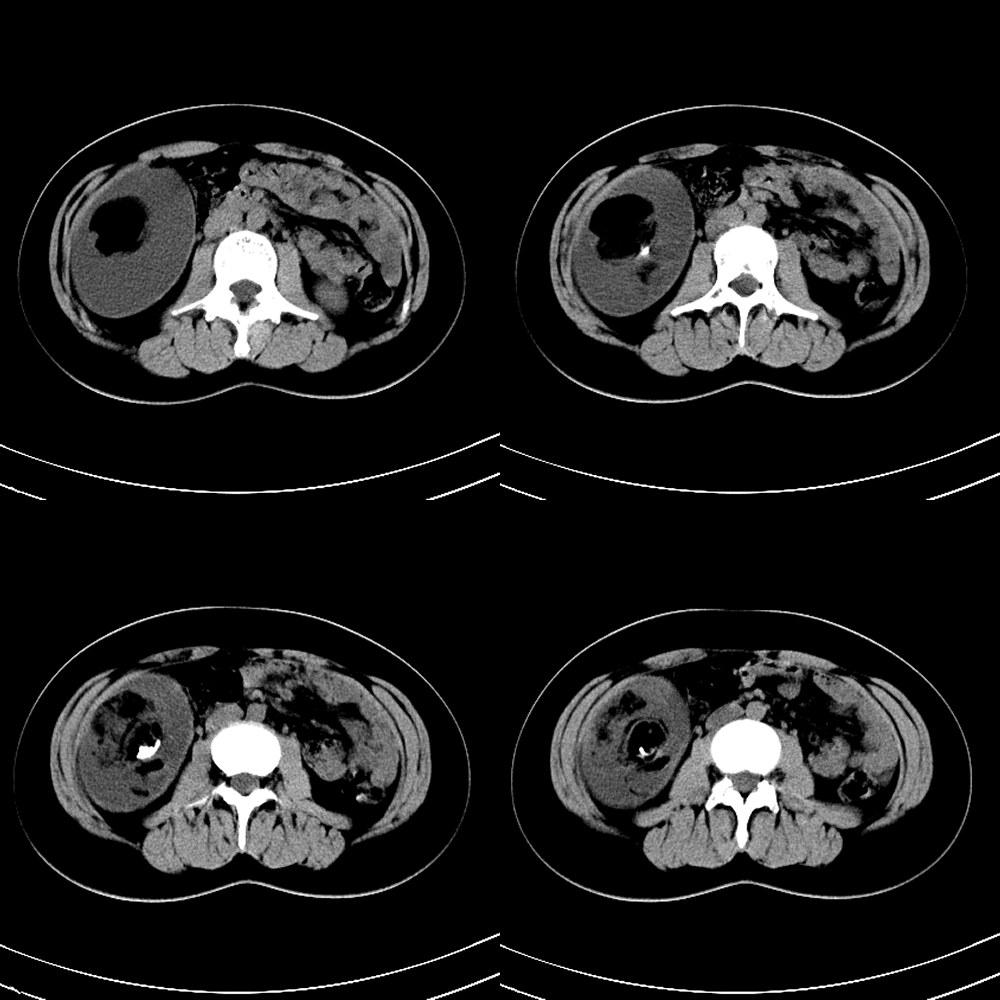

标题: CT13946:F18Y,一个典型病例。

f18y,无意中发现。无症状。典型病例,但是肿瘤定位在哪里?注:中心低密度ct值为-118hu.

注:中心低密度ct值为-118hu.

腹腔畸胎瘤 多考虑来源于肠系膜

腹膜后不能除外.

中腹部畸胎瘤以腹膜后多见。

腹膜后畸胎瘤

右侧腹膜后畸胎瘤。

典型畸胎瘤,考虑来源于右附件区。